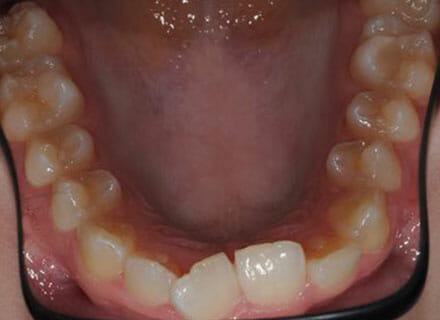

In this case, the upper incisors had a pushed back appearance and they were twisted. the smile was narrow – when the patient smiled the sides of the smile were in shadow. we used clear brackets to gently untwist and straighten the front teeth while widening the upper arch/jaw to broaden the smile. this patient was beaming for the first time in just 12 months.